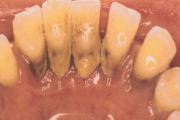

Krooniline parodontiit

Krooniline parodontiit on mikroobide poolt põhjustatud hammaste tugikudede põletik, mille tulemusena tekib progresseeruv alveolaarluu (nähtav röntgenograamil) ja periodontaalligamendi destruktsioon, igemetaskute moodustumine, igeme retsessioon või mõlemad kahjustused kombineeritult. Loe edasi »

- puudulik suuhügieen (5)

- igemepealne hambakivi (5)

- igemealune hambakivi (4)

- igemepiir on taandunud (3)

- luu destruktsioon (5)

- hamba kinnitussidemete kadu (3)